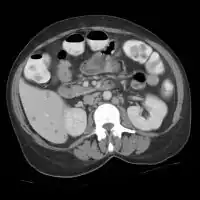

CT scan: Liver candidiasis - multiple small rounded foci in liver and spleen.

CT scan: Liver candidiasis - multiple small rounded foci in liver and spleen.